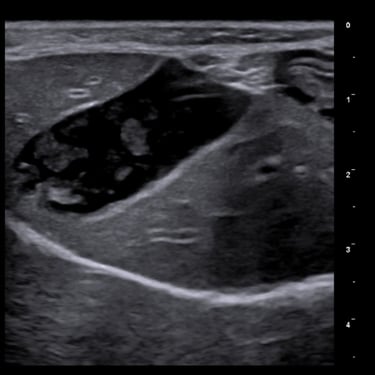

Practicing companion animal veterinary medicine in Simcoe County since 2012, Dr. Elyse is experienced in a variety of clinical settings from emergencies to chronic disease management and routine care.

Focusing on efficiency, workflow, and accuracy to provide actionable information to pet parents and veterinarians, while keeping patient wellbeing at the forefront.

Dr. Hauer has completed over 270 formal hours of continuing education in diagnostic abdominal and cardiac ultrasound from a variety of experts in the field, including a year-long immersive Advanced Imaging program through the Academy of Veterinary Imaging in Arlington, TX. She is a member of the International Veterinary Ultrasound Society.